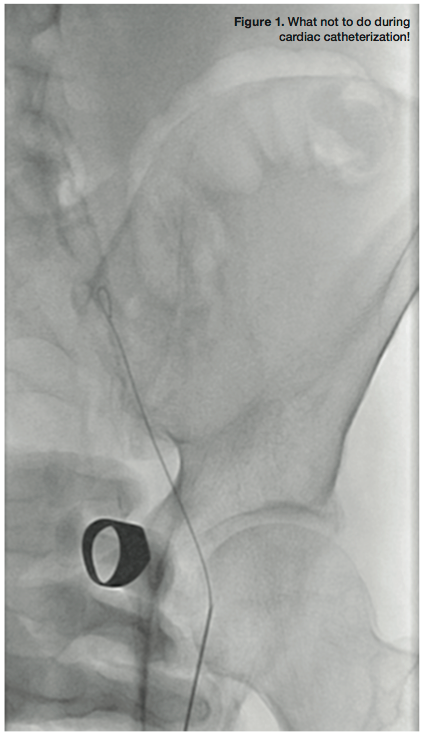

I frequently visit various cardiac catheterization laboratories both in the US and abroad and watch live cases at various interventional meetings. I find such experiences invaluable for “opening the mind” to new, different, and often better ways to do what we do every day. However, there is one aspect of the catheterization procedures that I often find discomforting: radiation safety practices vary widely and are often ignored. I recently observed an expert interventionalist skillfully complete two extremely challenging peripheral interventions. In both cases, his hands were in the middle of the radiation beam for several minutes (Figure 1)! The response to my pleas about this was: “I did not like it, but I had to do it.”

How can interventionalists reduce radiation exposure? The simplest first step is to not step on the fluoroscopy pedal when not looking at the screen. Although this appears self-evident, I remain amazed at how often this simple principle is ignored! Another obvious second step is to not insert our hands in the radiation field. Of course there are exceptions — occasionally in an arresting patient undergoing emergency PCI the hands of the person performing cardiac compressions may get in the beam — but this should be the exception, rather than the rule.